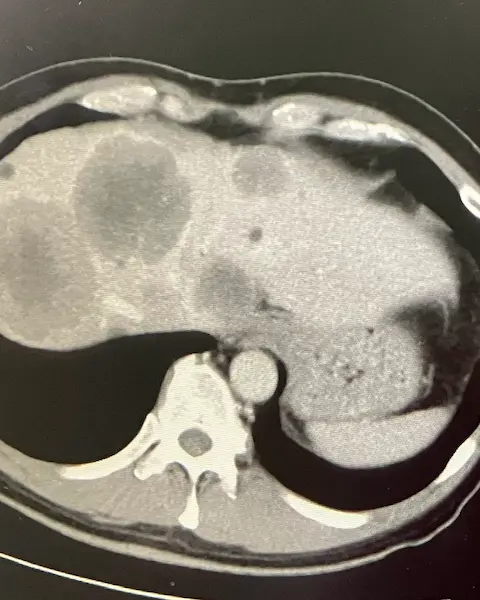

医師からそう告げられ、肝臓全体に転移したがんのCT画像を見せられた日のことは、今も忘れられません。

- 大腸がんステージ4

- 肝臓全体へ転移(手術はもう出来ない)

- (何もしなければ)余命半年

と診断されました。

CT画像で肝臓全体にがんが広がっていることを自分の目でも確認。